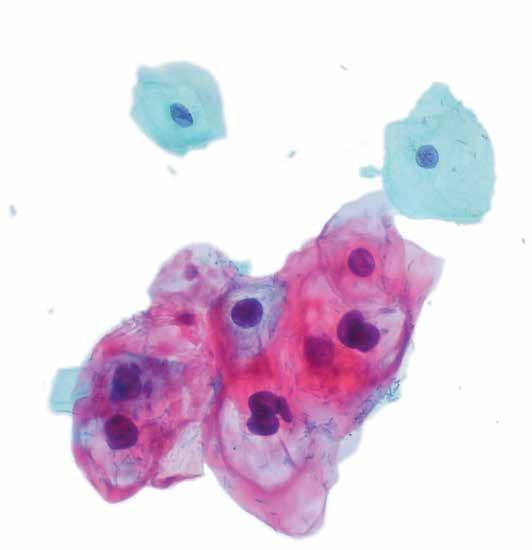

62 Vacina terapêutica testada em roedores eliminou tumores causados pelo vírus HPV